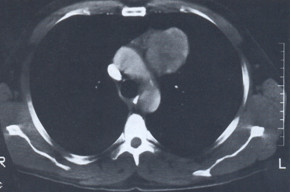

U chorego, lat 33, bez dolegliwości, w dobrym stanie ogólnym wykonano rutynowo rtg klatki piersiowej (przed rozpoczęciem nowej pracy), a następnie KT (obraz poniżej). Jakie jest najbardziej właściwe dalsze postępowanie?